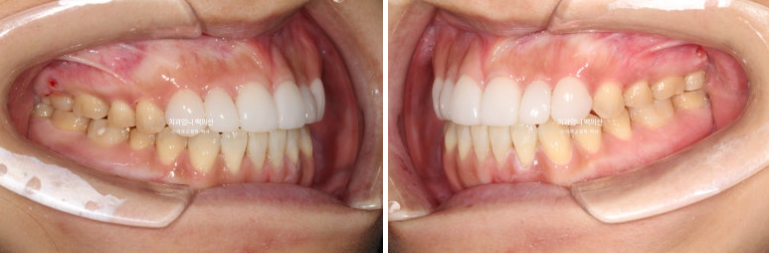

이제 전후비교 보겠습니다.

23.05~25.05

개방교합이 해소가 되었으니 이제 음식을 앞니로 베어드실 수 있게 되었습니다.

뿐만아니라 하관이 짧아지는 효과도 보실 수 있습니다.